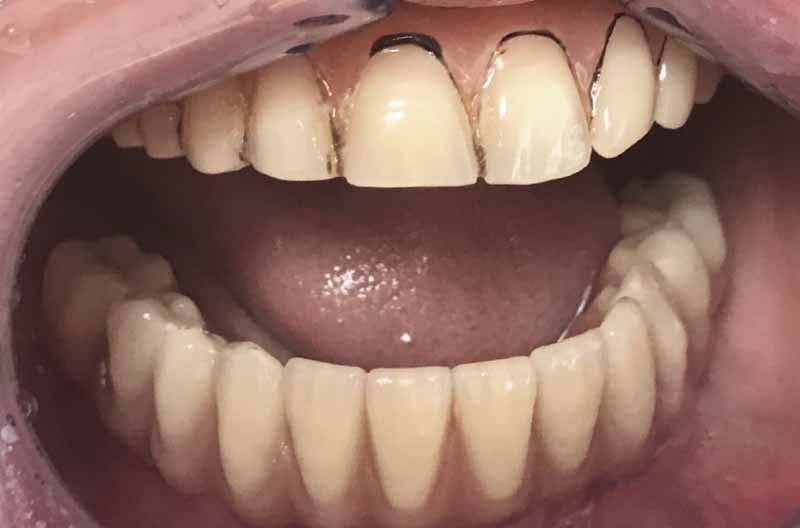

Questo case report riguarda una paziente di 54 anni che arriva alla nostra osservazione con una situazione estremamente compromessa nell’arcata inferiore, denti mobili e difficoltà a masticare (Fig. 1). La paziente era già stata in altra sede dove le avevano proposto un intervento di innesto osseo prelevato dalla cresta iliaca oppure una protesi totale rimovibile. La richiesta della paziente era una protesi fissa non rimovibile senza sottoporsi ad interventi invasivi di innesto osseo.

- Fig. 1